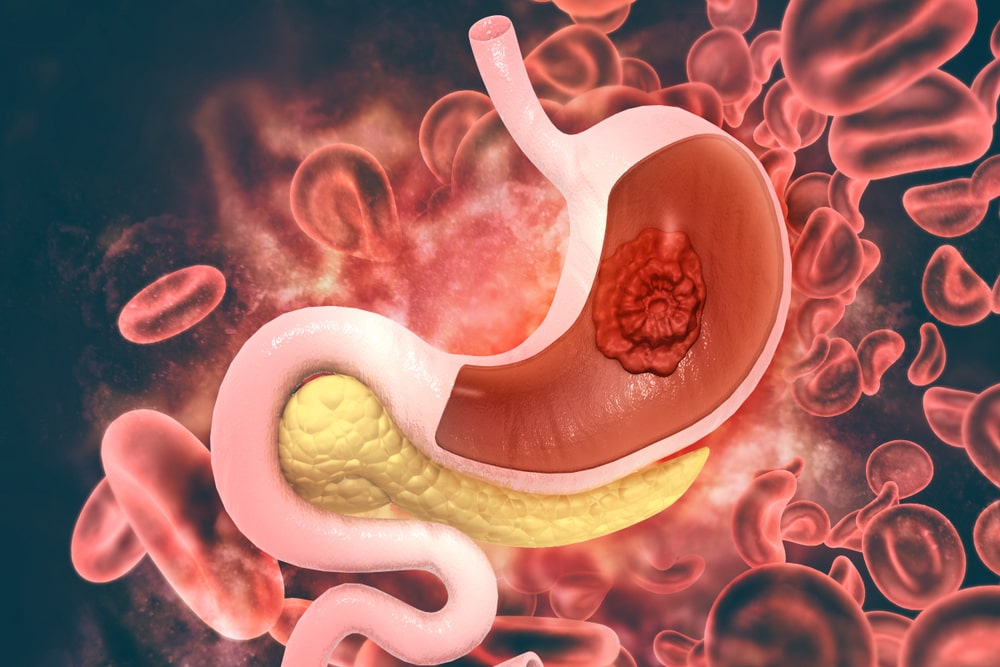

• Stomach Problem

Stomach Problem Gas, Acidity, GERD, IBS, Indigestion, Constipation, Piles, Fissures, Fistula, Mouth Ulcer-Stomatitis, Peptic Ulcer, Gastric Ulcer, Ulcerative Colitis, Hepatitis A-B, etc...